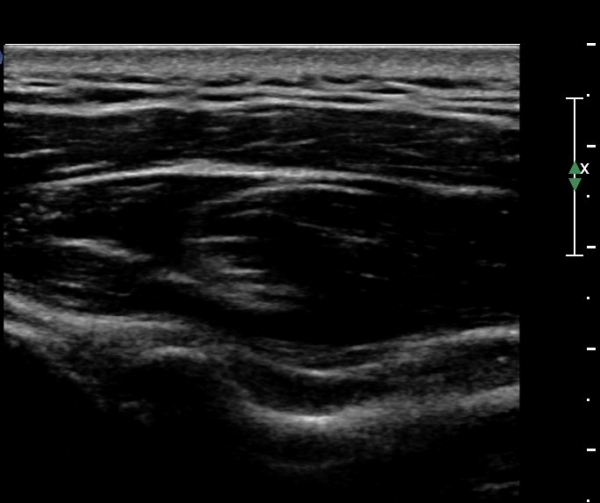

¾î±ú µÚÂÊ È¾´Ü¸é°Ë»ç¿¡¼­ °üÀý¿Í(glenoid) ³»Ãø¿¡¼­ ¸¹Àº ¾çÀÇ ¼ö¾×Àú·ù°¡ °üÂûµÈ´Ù(»çÁø 1, 2).